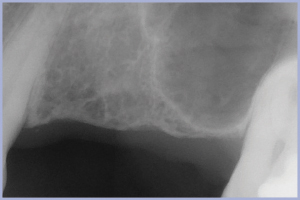

2° Caso – Zona 2.6, osso crestale residuo 3 mm

- Fig. 33 – Rx endorale preoperatoria eseguita secondo la tecnica parallela